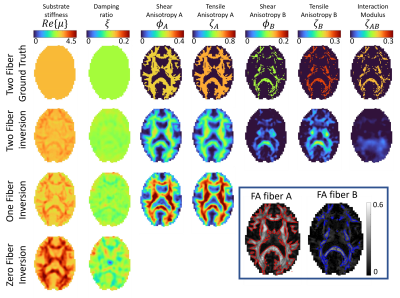

Simulated experiments: A realistic brain simulation generated form in vivo MRE3 with properties defining three classes of tissue, 0 fibers for FAA and FAB < 0.15, one fiber for FAA>0.15 & FAB<0,15, and two fibers for FAA>0.15 and FAB>0,15. Zero, one and two-fiber nonlinear inversion (NLI) property recovery algorithms were run to investigate performance when regions of different fiber counts are present.

The new two-fiber model does show some promise, with reasonable performance in the simulated data shown in figure 2, and in vivo images in figure 4 show structure and symmetry. The loss of resolution in the moving from the one-fiber to two-fiber models shown in figure 4 suggests we are getting close to the limit of achievable complexity for MRE in these anisotropic models. A multi-model approach where the number of fibers varies based on DTI two-fiber fractional anisotropy maps may help by reducing unnecessary unknowns where they are not required. The hierarchical structure of the model presented here will be valuable as elasticity matrix terms can be truncated when a fiber isn't present.

Figure 2: Two fiber brain simulation, where ground truth tissue properties with both FA<0.15 are isotropic, tissues with FAA>0.15 and FAB<0.15 have one fiber, and tissues with FAB>0.15 have two-fibers (see lower right box for maps). A single representative slice of full-brain simulated data is shown. NLI inversions with two-fiber, one-fiber (TI-NLI) and zero-fiber inversions are shown. Other than the interaction moduli, ζAB, two-fiber inversions are spatially accurate with some incomplete contrast recovery. Neglecting fibers causes artifacts and missing information.

Figure 4: In vivo inversions of a healthy brain with 0 fiber (isotropic), one fiber (transverse isotropic) and two-fiber NLI inversions. Property maps are symmetric and show anatomical structure. The effective resolution changes as different fiber families are added, likely due to model-data mismatch combined with more difficult inversions for more complicated models.